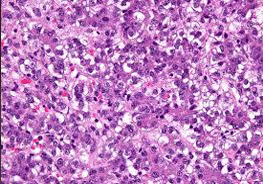

Other common cancers in children include lymphoma (cancer involving the lymph nodes), brain tumors, bone tumors, tumors of kidney or adrenal gland, soft tissue sarcomas, tumors involving the eyes, liver etc.